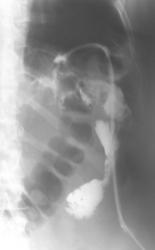

помогите разобраться имеется ли свищ толстой кишки

Как представляекся - оперативное вмешательство на желудке? Сейчас контрастной вещество в основном контрастировало развитую систему свищевых ходов в левом поддиафрагмаальном пространстве. Считаю, что сообщение с просветом поперечной ободочной кишки есть, но основная масса контрастного вещества располагается рядом с нисходящей кишкой. Доказательств  сообщения ходов с протоками панкреас не видно, но она в таких ситуациях принимает участие очень часто... Попытался бы применять встречное контрастирование - все повторить совместно с ирригоскопией, но гарантии в таких случаях не даст никто. Ищи - свищи....

Оперативное вмешательство  в октябре 2009г по поводу гемангиомы левой доли печени в объме резекции левой доли печени и хвоста поджелудочной железы, дренирование поддиафрагмального пространства. Сброса воздуха по дренажу никогда не отмечала.